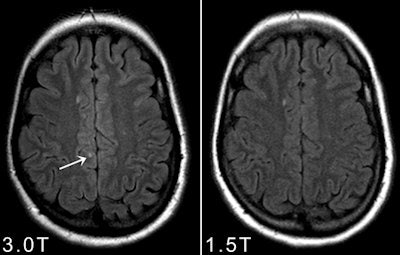

Axial double inverison recovery images at 1.5-tesla and 3-tesla in a patient with multiple sclerosis. Please note that at 3-tesla more cortcial gray matter lesion can be identified."We should ask ourselves whether it is necessary and useful to formally test all possible differences in terms of diagnostic accuracy between both field strengths. Advantages and disadvantages of higher magnetic field strengths are well known and incontestable. The higher SNR at 3 tesla allows imaging at a higher spatial resolution and the application of parallel imaging techniques as well as routine use of 3D sequences," they wrote.